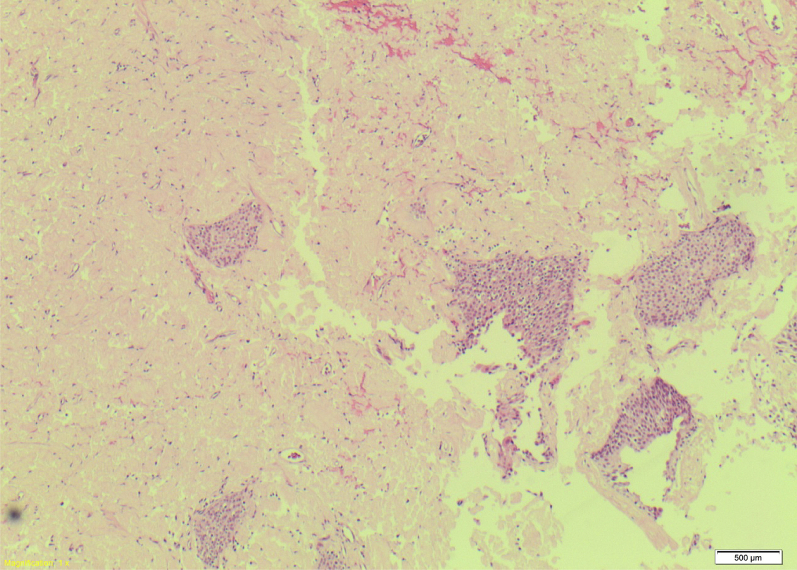

Figure 1.

Bladder biopsy section. Haematoxyline & Eosin section illustrates dense amphorous pink acellular material with the presence of an edge of benign uroithelium.